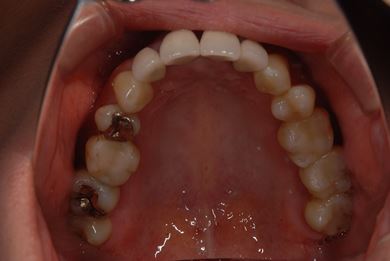

| 性別/年齢 | 女性 / 40歳 | ||||||||||||||||||||||||||||||||

| 主訴 | 前歯のつけ根の黒い部分を見えないようにしたい。 | ||||||||||||||||||||||||||||||||

| 治療方針 | 上顎前歯をセラミック治療にて審美的回復を行う。 | ||||||||||||||||||||||||||||||||

| 治療内容 | オールセラミッククラウン4本(セラミック用土台4本) | ||||||||||||||||||||||||||||||||

| 総治療費 | 573,300円 | ||||||||||||||||||||||||||||||||

| 治療期間 | 3ヶ月 |